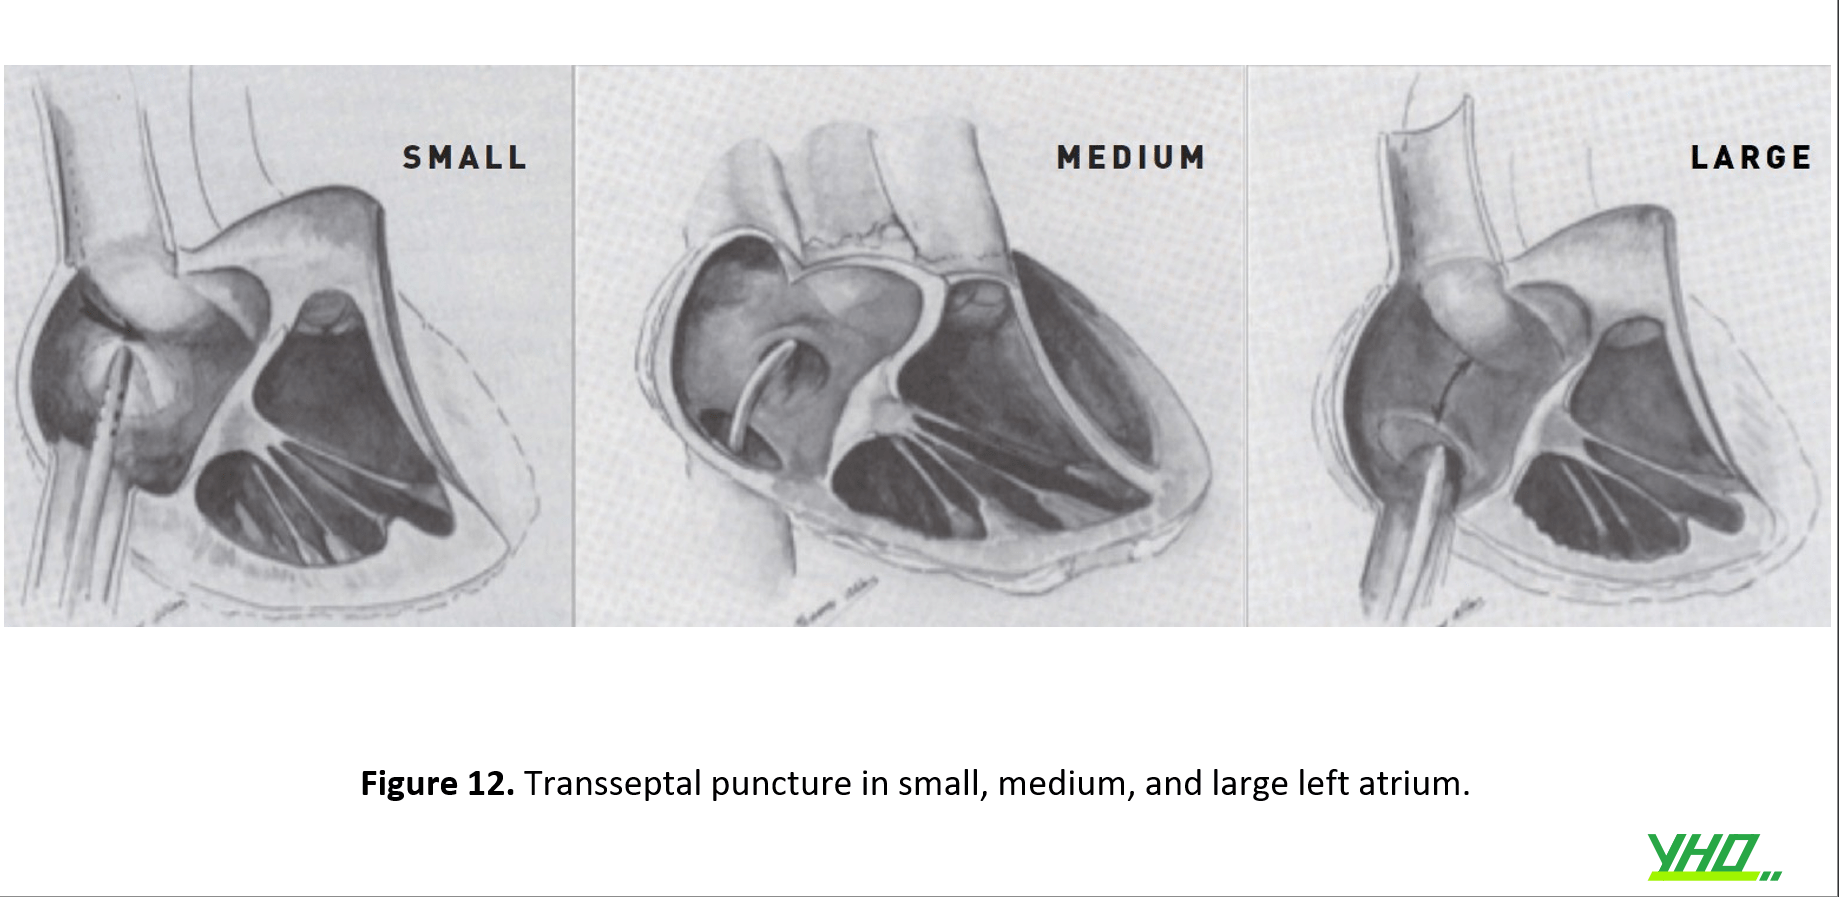

Trong bệnh van tim, vị trí của lỗ bầu dục có thể thay đổi, và việc đâm xuyên có thể thực hiện thành công bên ngoài lỗ. Khi LA dãn, hố bầu dục có xu hướng dịch chuyển về phía dưới.(hình 12)

Một tâm nhĩ trái khổng lồ có thể được cho là làm cho việc chọc thủng vách ngăn dễ dàng hơn, nhưng điều ngược lại thường xảy ra. Có thể rất khó tìm được điểm bắt trên vách ngăn bằng ống thông hoặc đầu kim. Thông thường, phải sử dụng vị trí thấp bất thường, tránh quá sau, trên vách ngăn.(hình 12)